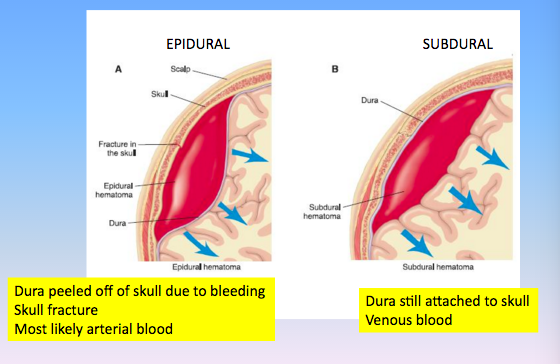

Describe the differences:

Epidural vs Subdural

2

See picture

Epidural

- Above the dura

- Respects suture lines

- High force trauma

- Arterial blood (commonly the middle meningeal artery)

- Lentiform (lens-shaped) or biconcave on CT

- Acute presentation

Subdural

- Below the dura

- Doesn’t respect suture lines

- Low force trauma

- Venous (from venous plexus)

- Cresent (banana-shaped) on CT

- May be insidious (worsening headache over days)